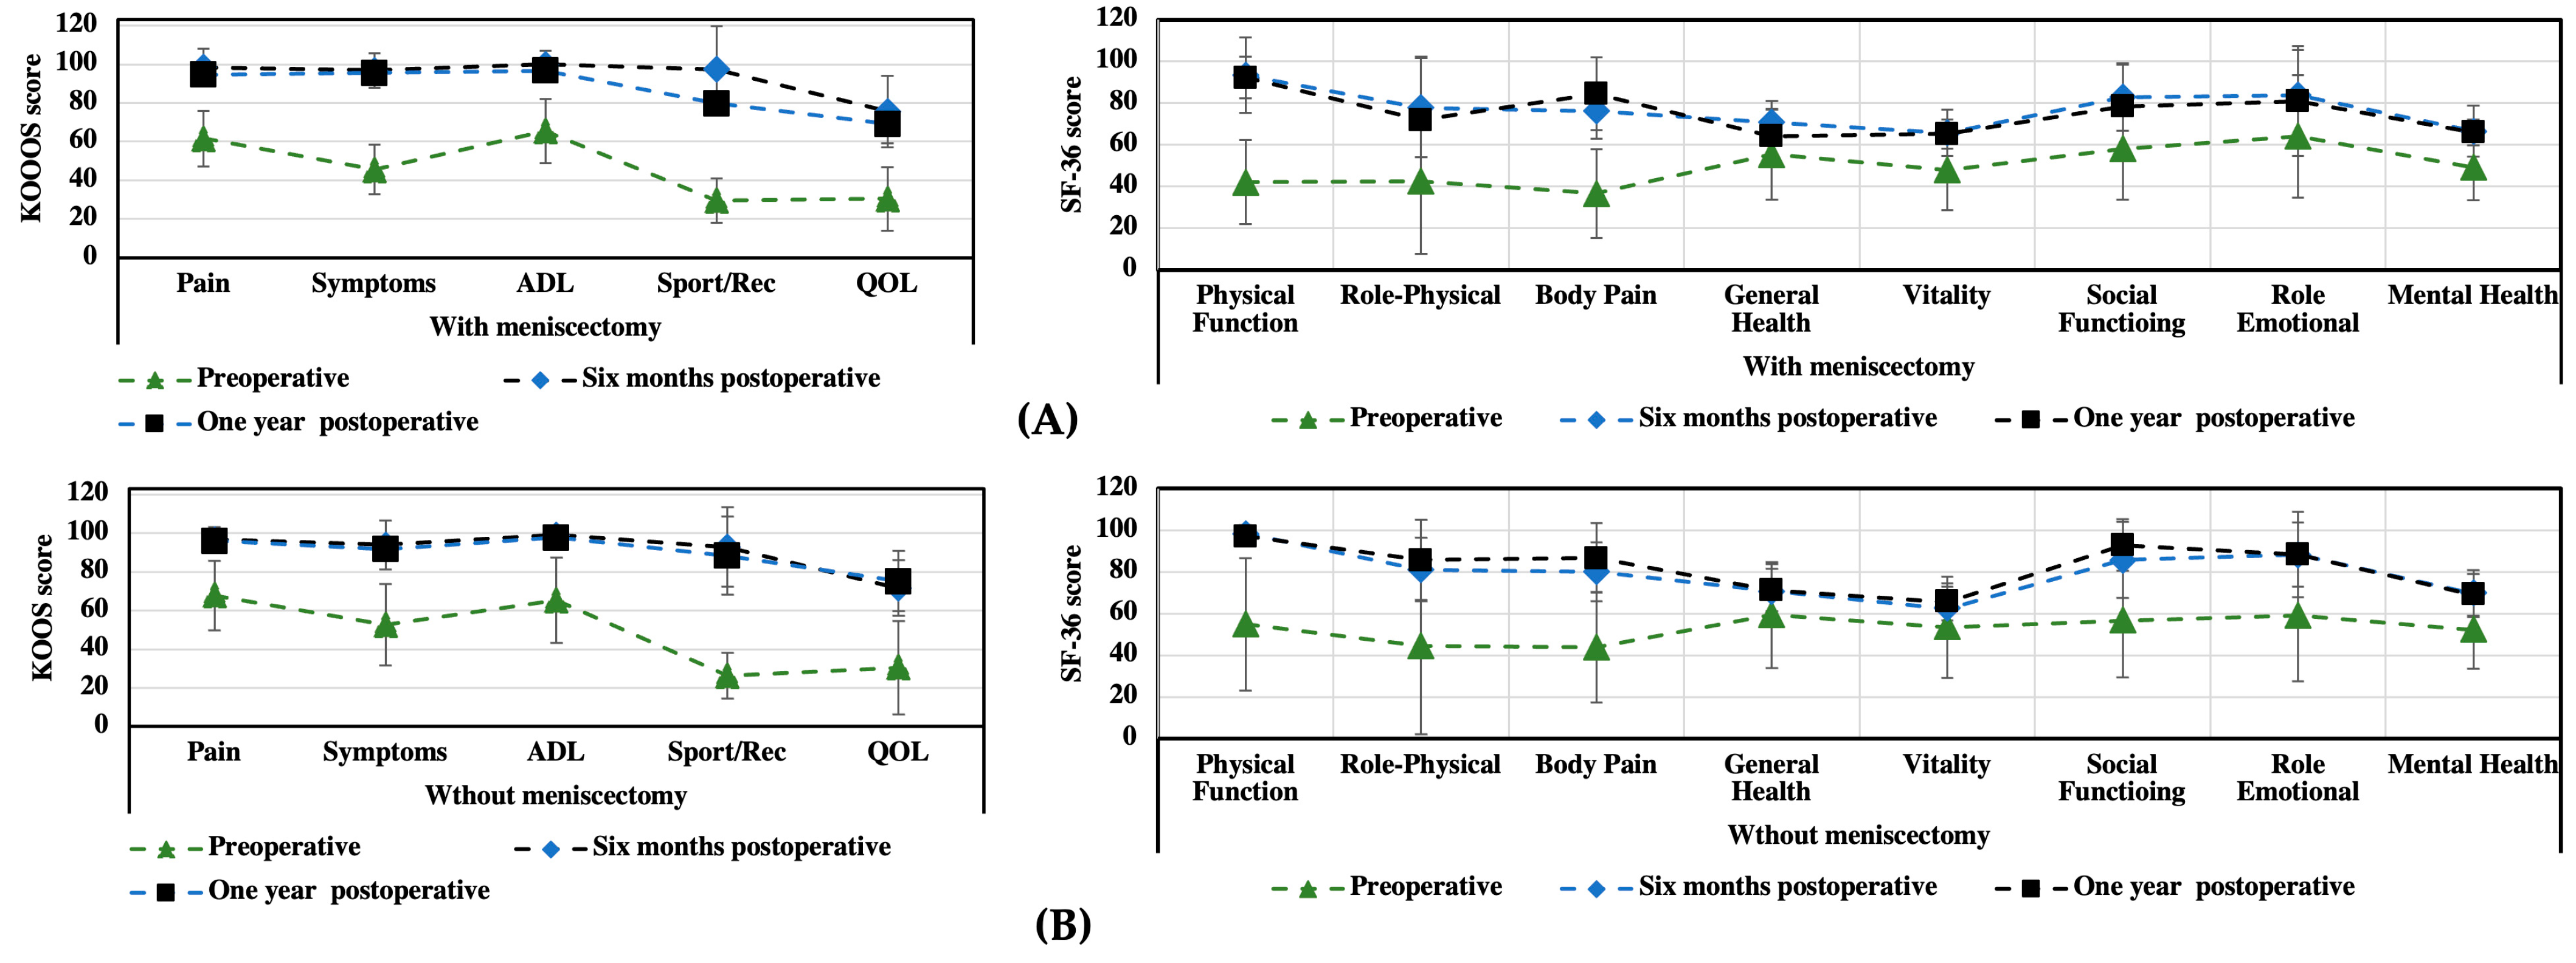

3.1. KOOS and SF-36 Scales

3.2. Functional Assessment

| Preoperative | Six Months Postoperative | One Year Postoperative | (before/after Six Months) | |

|---|---|---|---|---|

| KOOS | Mean ± SD | Mean ± SD | Mean ± SD | p |

| Patients (n) | 49 | 49 | 43 | |

| Pain intensity | 55 ± 18.2 | 96 ± 4.2 | 99.5 ± 2.3 | <0.05 |

| Symptoms | 46 ± 16.6 | 93 ± 6.5 | 98.2 ± 1.8 | <0.05 |

| Activities of daily living | 57 ± 25.5 | 99 ± 2.6 | 100 ± 0.0 | <0.05 |

| Sport/Rec | 14 ± 11.1 | 95 ± 7.7 | 99.8 ± 1.8 | <0.05 |

| Quality of life | 30 ± 18 | 76 ± 4.7 | 88 ± 8.8 | <0.05 |

| Preoperative | Six Months Postoperative | One Year Postoperative | ||

|---|---|---|---|---|

| SF-36 | Mean ± SD | Mean ± SD | Mean ± SD | (before/after Six Months) |

| Patients (n) | 49 | 49 | 43 | p |

| Physical function | 34 ± 18.5 | 95.6 ± 2.0 | 97 ± 2.5 | <0.05 |

| Role physical | 63 ± 46.5 | 76 ± 15.0 | 96 ± 3.7 | 0.345 |

| Bodily pain | 36 ± 18.7 | 78 ± 15,6 | 98 ± 2.3 | <0.05 |

| General health | 68 ± 17.1 | 70 ± 16.1 | 83 ± 15.8 | 0.401 |

| Vitality | 53 ± 20.6 | 64 ± 8.0 | 87 ± 7.1 | 0.067 |

| Social function | 64 ± 29.6 | 87 ± 13.6 | 90 ± 9.5 | 0.068 |

| Role emotional | 73 ± 42.0 | 83 ± 22.9 | 90 ± 13.3 | 0.285 |

| Mental health | 52 ± 9.8 | 68 ± 11 | 70 ± 10.8 | 0.464 |